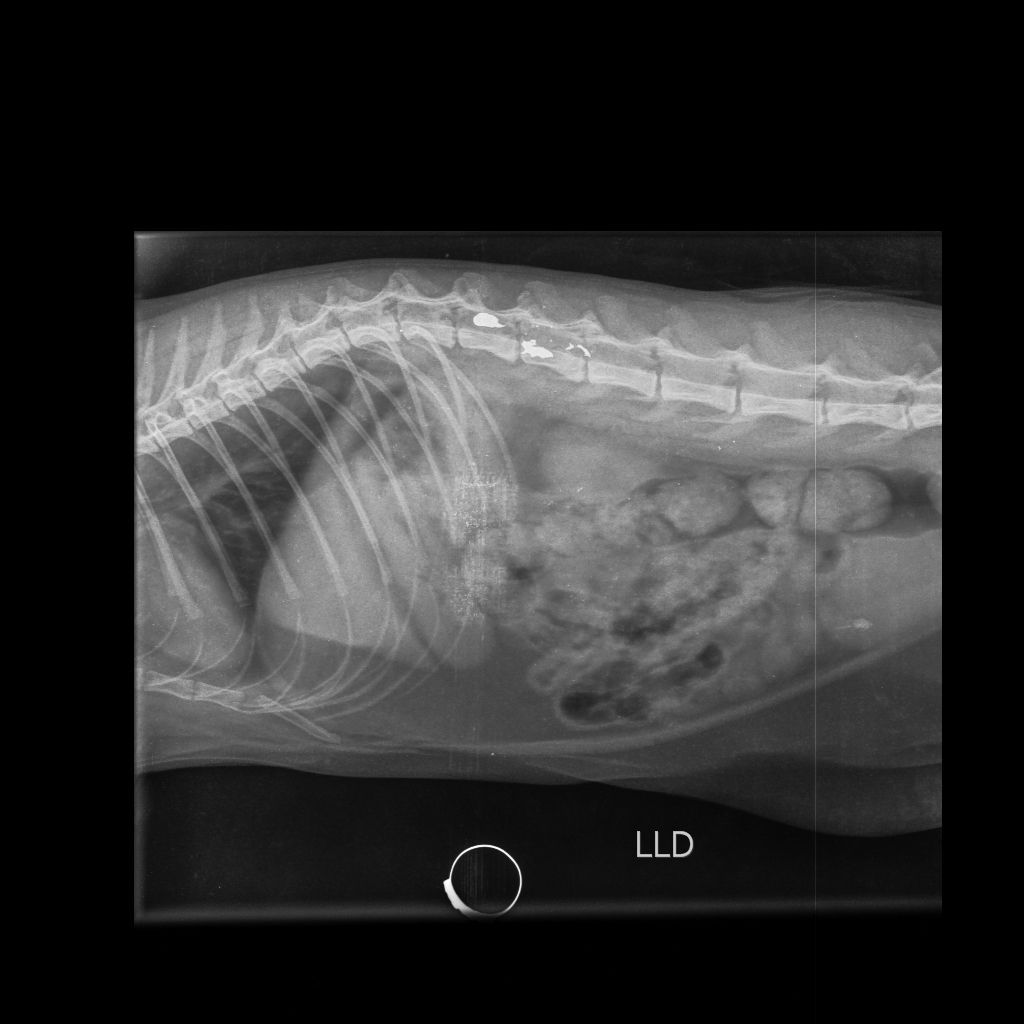

A gata foi socorrida e encaminhada para atendimento veterinário na clínica Vida Pets, onde recebeu os cuidados necessários. O animal passou por exames e procedimentos médicos após o disparo, enquanto os tutores prestaram depoimento às autoridades e acompanharam o andamento das investigações.

A gata Morgana segue internada sob cuidados veterinários e, segundo os tutores, a previsão é de que ela receba alta na próxima segunda-feira (09). Até o momento, o animal permanece em estado estável, porém ainda apresenta algumas complicações e não tem se alimentado adequadamente. A gata está sendo acompanhada de perto por profissionais da clínica e conta também com a supervisão de um médico neurocirurgião veterinário de Foz do Iguaçu-PR. A família informou que somente após a alta médica será possível avaliar com mais precisão as possíveis consequências causadas pelo projétil. Os tutores também afirmaram que pretendem continuar acompanhando o caso e buscar a responsabilização do autor do disparo, reforçando o agradecimento à mobilização da comunidade e aos veículos de comunicação que deram visibilidade ao ocorrido.